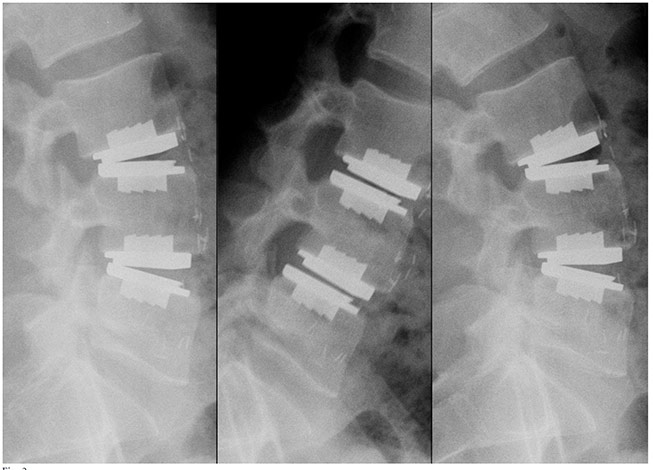

The prodisc L Anterior Lumbar Total Disc Replacement is a motion-preserving surgical procedure used to treat damaged lumbar discs that cause chronic lower back pain. It involves removing the affected disc through a small anterior (front) incision and replacing it with the prodisc L implant, an FDA-approved artificial disc designed to maintain natural spinal movement. This approach can relieve pain while avoiding the stiffness commonly associated with spinal fusion in appropriately selected patients.

Beginning with clinical usage in 1990, the prodisc design has been validated with over 225,000 device implantations worldwide and more than 540 published papers (PubMed, Embase, Ovid Medline®).

prodisc L Gallery

Click to enlarge image